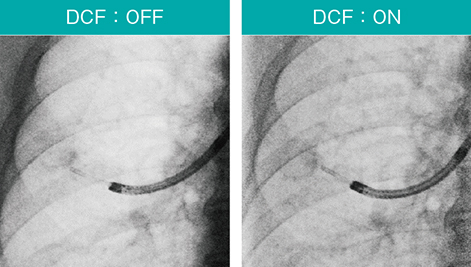

Ultimax-iの高画質・低線量検査コンセプト「octave SP」は、独自のリアルタイム画像処理技術と低線量検査のための機能によって、従来より65%被ばくを低減する(従来の35%の線量)と同時に、ノイズ低減と低コントラスト改善による高画質を実現する。例えば、DCF(デジタル補償フィルタ)の適用により、肋骨のラインや腫瘤陰影の濃度、ガイドシースなどが明瞭に確認できる(図6)。

図6 DCF(デジタル補償フィルタ)適用例

肺野が白とびせず、病変・シースが見やすい。

Accent適用、スコープ:BF-P290、ガイドシース:SG-400C(オリンパス社製)